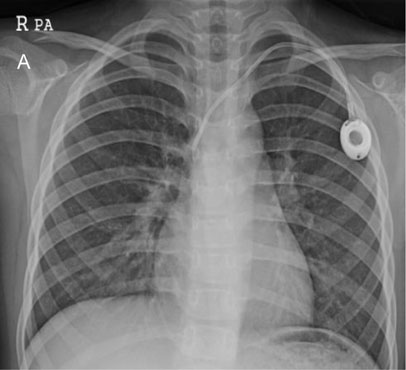

Fig. 2-A

TIVD inserted through left IJV before a removal operation.

jkaps-18-18-g004.jpg

Fig. 2-A TIVD inserted through left IJV before a removal operation.